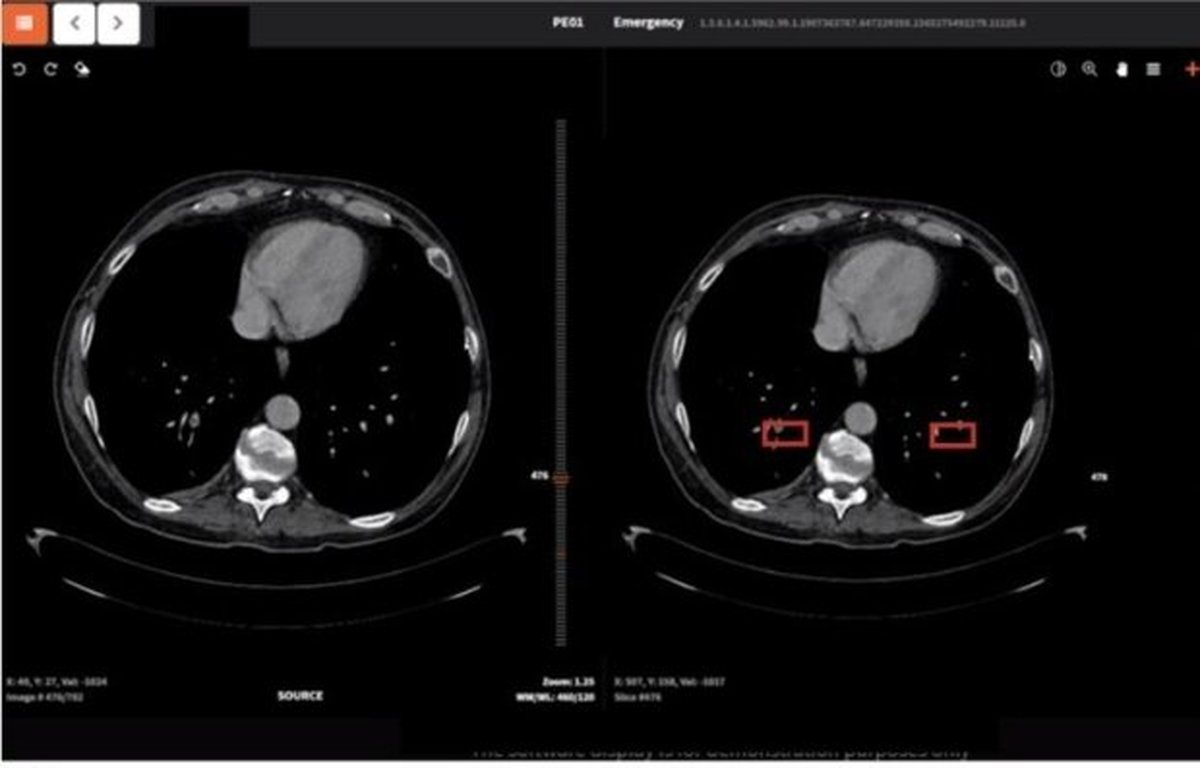

وی در ادامه عنوان کرد: کشور چین از هوش مصنوعی برای تشخیص این بیماری استفاده کرده است و یک شرکت برخاسته از دانشگاه استنفورد آمریکا نیز فعالیتهایی را در این زمینه انجام داده است. ما نیز با تمرکز بر روی کاربرد هوش مصنوعی در سی تی اسکن، با نوآوری سامانهای را برای تشخیص سریع و با دقت کووید ۱۹ طراحی کردهایم که قابلیت تخمین حجم ناحیه عفونی را نیز داراست.

رئیس گروه علم و فناوری اطلاعات و ارتباطات جایزه مصطفی (ص) همچنین افزود: سیستمهایی که در کشور چین یا آمریکا استفاده میشود، دقتی بالای ۹۰ درصد دارند. این سامانه که حاصل نبوغ جوانان دانشمند ما است با پیش پردازش نوآورانه بر روی تصاویر سیتی اسکن و استفاده از راهکارهای توصیف پذیری در یادگیری ماشینُ، سامانهای با دقت و حساسیت بالاتری را به وجود آورده است.

به گفته وی سامانهای که این تیم تحقیقاتی براساس هوش مصنوعی طراحی کرده است با نوآوری در پیش پردازش و پردازش تصاویر در شبکههای عمیق توصیف پذیر، توانسته است به صورت پایدار و در زمانی کمتر از یک دقیقه، نتایج خوب و با دقت و حساسیت بالای ۹۷ درصد را به دست آورد؛ علاوه بر این سامانه حجم نواحی عفونی را نیز محاسبه میکند.

وی با بیان اینکه کووید ۱۹ در برخی از تصاویر در مراحل اولیه بیماری با چشم غیرقابل مشاهده است، تصریح کرد: از بیمارستانهای مختلف، نمونههایی را داشتهایم که امکان تشخیص این بیماری برای آنها از مشاهده تصاویر وجود نداشته است اما سامانه هوشمند ایرانی باتوجه به طراحی مناسب آن توانسته است بیماری را در مراحل اولیه تشخیص دهد.